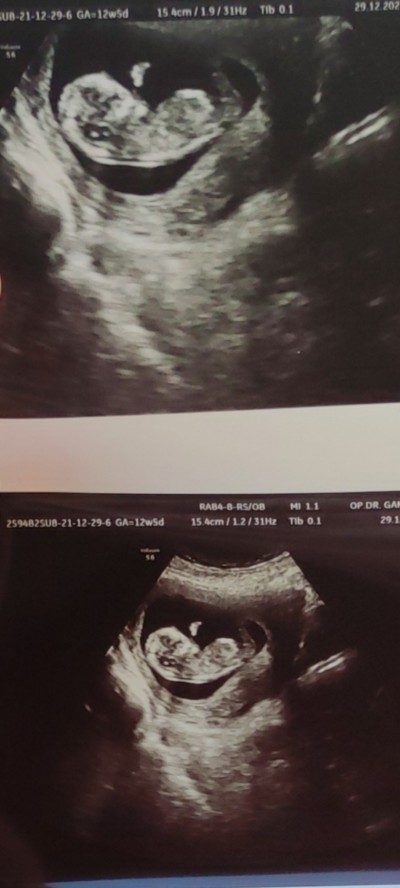

image

13+2 burda  dün gitim ama söylemedi doktor:(

Numaracııı  :) 2 tane var daha bebekler, dedim bu kız yine mi hamile :D

Ne numarası kız teeee ocakta attığım şey :D sjsj